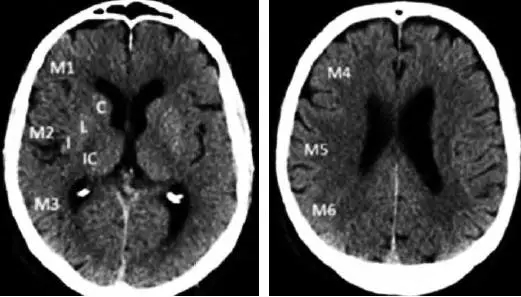

3.2.1 ASPECTS评分

ASPECTS评分是基于NCCT评估MCA区域早期缺血改变简单而系统的一种方法[22]。将MCA供血区各主要功能区分别赋分(4个皮层下区:尾状核C、豆状核L、内囊IC、岛叶I;6个皮层区,标志为M1-M6)(图1),共计10分,每累及一个区域减去1分,即正常脑CT为10分,MCA供血区广泛梗死则为0分。

图1. ASPECTS评分中大脑中动脉供血区功能分区

注:皮层下区:C:尾状核(caudate);L:豆状核(lentiform);IC:内囊(internal capsule);I:岛叶(insular ribbon);皮层区:M1-M6。ASPECTS:Alberta卒中项目早期计算机断层扫描评分